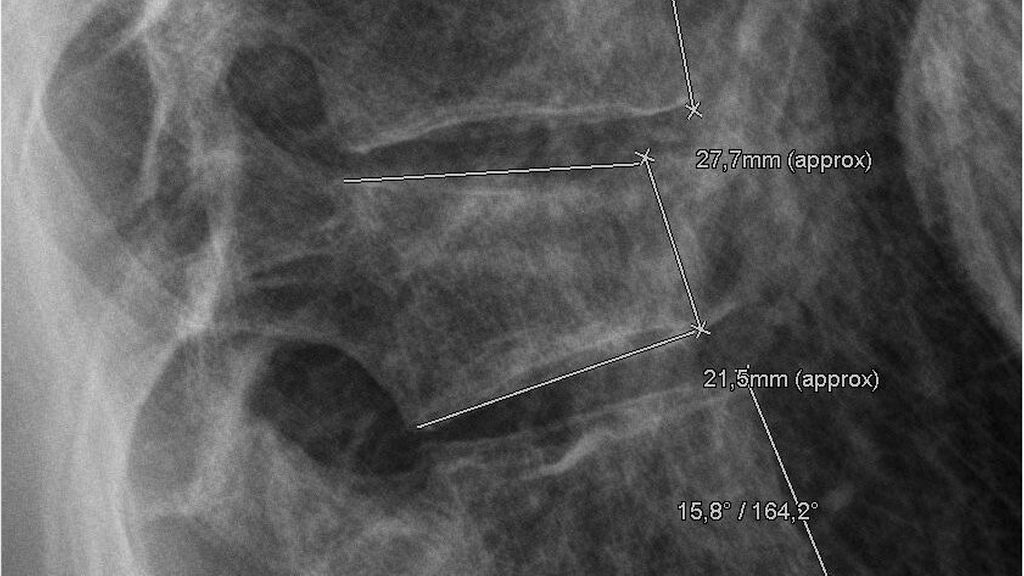

Das klinische und radiologische Follow-up erfolgte nach frühestens 3 Monaten. Die radiologische Vermessung erfasste sowohl den lokalen und segmentalen Kyphosewinkel nach Cobb als auch die Wirbelkörperhöhe zu vier Zeitpunkten (präoperativ, postoperativ, 3 Monate postoperativ sowie gegebenenfalls auch vor Metallentfernung), ausgedrückt durch die VBCR („vertebral body compression rate“) und die AVBC („anterior vertebral body compression percentage“). Um ein möglichst homogenes Patientenkollektiv zu analysieren, kamen stringente Ein- und Ausschlusskriterien zur Anwendung, welchen 42 Patienten entsprachen (u.a. waren atraumatische Frakturen, mehrsegmentale Stabilisierungen, zementierte Schrauben und Revisionsoperationen ausgeschlossen).

Es erfolgte bei 12 Patienten eine bisegmentale dorsale Stabilisierung ohne additive Ballonkyphoplastie (BK) (Kontrollgruppe) sowie bei 30 Patienten eine dorsale Stabilisierung mit additiver BK (Studiengruppe), die Patienten hatten ein Durchschnittsalter von 44,6 bzw. 52,9 Jahren. Der lokale Kyphosewinkel ließ sich durch die additive BK (Studiengruppe) unmittelbar postoperativ um im Mittel 9,25° steigern (präoperativ: 12,6°±4,81° zu postoperativ: 3,35°±4,79°, p=0,001). Auch bei Patienten ohne BK (Kontrollgruppe) wurde eine signifikante Zunahme des lokalen Kyphosewinkels um 5,3° beobachtet (präoperativ: 9,95°±6,59° zu postoperativ: 4,65±2,15°, p=0,003). Im Rahmen des 3-Monats-Follow-ups hatte sich sowohl bei Patienten mit BK als auch bei jenen ohne BK der lokale Kyphosewinkel an die präoperativen Parameter angenähert (Studiengruppe: 10,5°±5,0° bzw. Kontrollgruppe: 9,15±4,91°). Ähnlich verhielten sich sowohl die VBCR als auch die AVBC. Es wurden keine zementassoziierten Komplikationen im Rahmen der additiven BK dokumentiert.